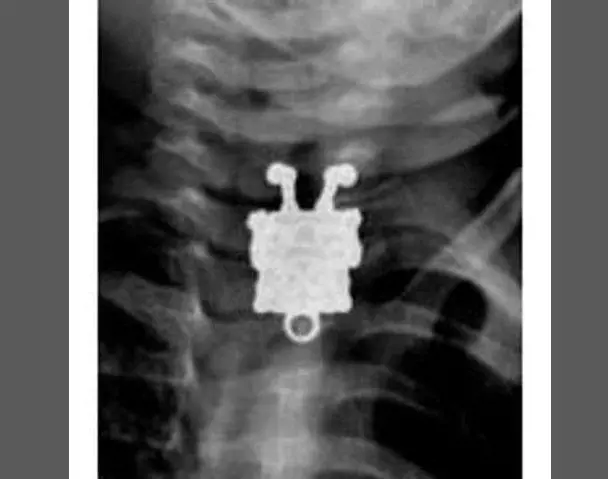

Pazze radiografie: gli oggetti che possono finire nel corpo umano

Oggetti bizzarri che hanno trovato la loro strada all'interno del corpo umano, e documentati grazie alle pazze radiografie raccolte dal dottor Frank Gaillard. Quest’ultimo ha fondato Radiopaedia.org, un sito collaborativo che raccoglie casi radiologici e articoli medici a tema.